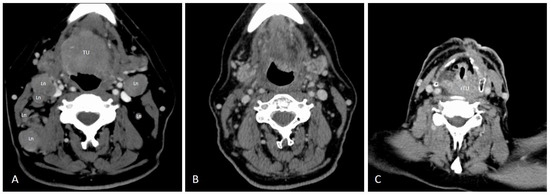

| Patient 1–5 | UICC | Age at Diagnosis | ASA Score | HPV Pre-Treatment | Therapy | HPV Post-Treatment | Course of Disease |

|---|---|---|---|---|---|---|---|

| Patient 1 | Stage III | 55 | 2 | HPV 16 | RCT | HPV 16 | Recurrence |

| Patient 2 | Stage I | 54 | 2 | HPV 16 | Surgery and PORT | HPV 16 | Pulmonal metastasis Locoregional control |

| Patient 3 | Stage III | 73 | 3 | HPV 16 | RCT | HPV 16 | Recurrence |

| Patient 4 | Stage IV | 86 | 2 | HPV 33 | CT only | HPV 33 | Tumor progression |

| Patient 5 | Stage III | 70 | 2 | HPV 18 | RCT | HPV 18 | Recurrence after partial response |